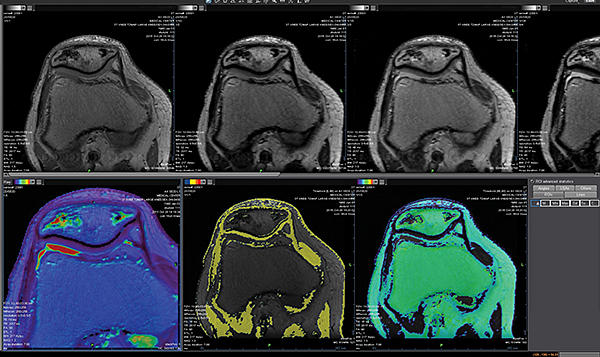

Додаток Prostate Streamlined.

Спеціальні програми Olea SphereTM для аналізу передміхурової залози включають в себе розширені можливості для оцінки дифузії та якісної оцінки перфузії. Також пропонують ефективний мультипараметричний аналіз усіх доступних послідовностей для візуалізації простати. В додатках реалізовано аналіз кінетики та кількісних даних на основі надійних математичних моделей. Програми передміхурової залози включають звіт PI-RADS® 2 для покращення виявлення, характеристики та вірогідності встановлення діагнозу раку простати. Цей програмний пакет стандартизує виклад протоколів опису, а також вказує рівень підозри або ризик виникнення клінічно значущих пухлин.